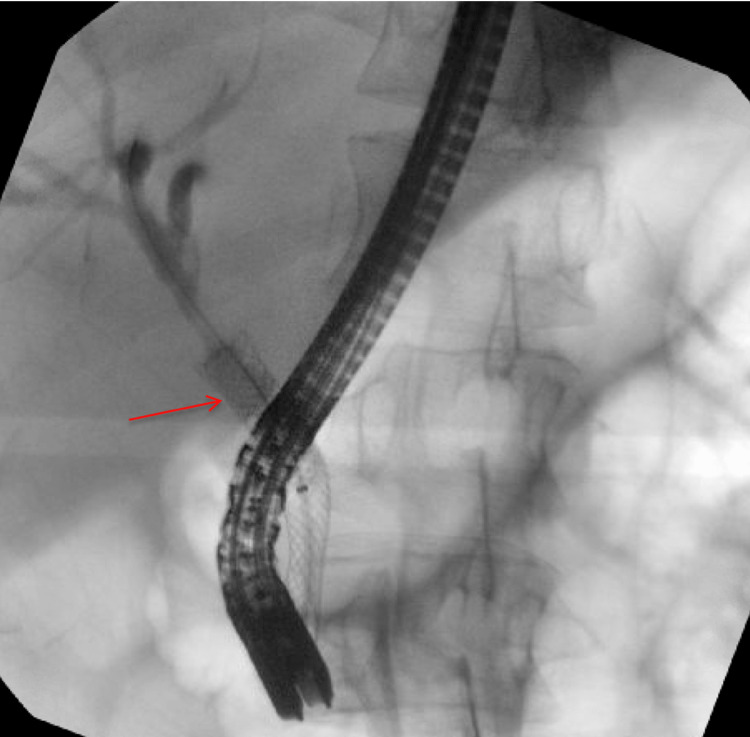

An MRCP demonstrated choledocholithiasis within the distal common bile duct (CBD) with significant intra and extrahepatic ductal dilation (Figure 2). He underwent an endoscopic retrograde cholangiopancreatography with sphincterotomy. Multiple stones were removed; however, due to concern for residual retained stones, a 10 French fully covered metal endobiliary stent was placed (Figure 3). A prophylactic plastic endopancreatic stent was also placed in the dorsal pancreatic duct due to incidental cannulation.